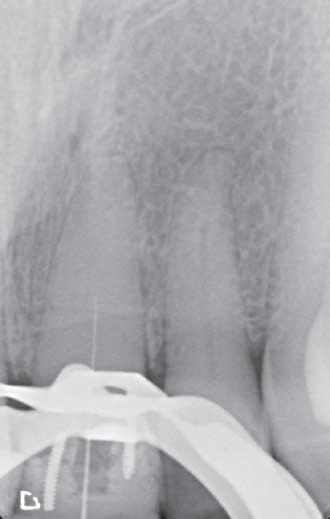

The patient returned in May 2024 reporting a history of slight discomfort

from the tooth. In the intervening two years, the patient’s dentist had applied a composite build-up, secured using two pins, making the UL1 heavily restored. A new CBCT scan showed severe calcification of the root canal, and a lateral radiolucency mid-root on the distal aspect (marked with red arrow) (Figure 2).

The HyFlex OGSF sequence from COLTENE was the system of choice for this procedure, due to the system’s excellent cutting efficiency. All of the files in the sequence, consisting of an Orifice Opener, Glidepath File, Shaping File and Finishing File were employed, with irrigation between each file. Locating the canal was challenging due to the extent of the calcification. Establishing the location took time, and required a dental microscope. Once the tooth was opened with the Orifice Opener, it was over to a MicroMega K-File ISO 08 to reach as deep down as possible into the canal. Then it was the turn of the Glidepath File, 1mm short of the length achieved with the K-File, and this process was repeated all the way to the root apex.

Once the root was open, the Shaping

File was utilised, ending with the 30/.04 Finishing File to clean out the canal, completing the OGSF sequence. The canal was irrigated using COLTENE CanalProTM NaOCI 3% during the instrumentation and COLTENE CanalProTM EDTA as a finial irrigation. The tooth was restored using a glass ionomer cement, and the patient went back to the dentist for the final restoration.

3: Periapical X-ray to check orientation of file